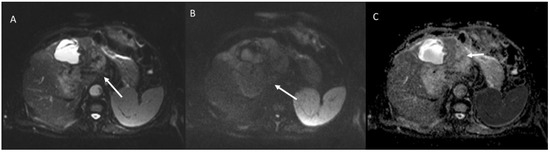

- Granata, V.; Fusco, R.M.; Catalano, O.; Filice, S.; Avallone, A.; Piccirillo, M.; Leongito, M.; Palaia, R.; Grassi, R.; Izzo, F.; et al. Uncommon neoplasms of the biliary tract: Radiological findings. Br. J. Radiol. 2017, 90, 20160561. [Google Scholar] [CrossRef] [PubMed]